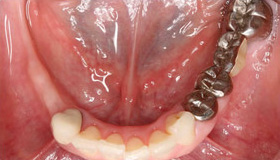

治療前

初診時:右下の奥歯を4本喪失した状態です。レントゲンでは、延長ブリッジが虫歯になり、歯との隙間が確認できます。

骨量が不足し、下顎の太い神経である下歯槽神経までの有効な骨の高さを正確に把握する必要があり、CTレントゲンでの精査をし、そのデータ上でインプラント治療の計画を立てました。1次オペ:骨幅が足りない部分に、骨再生のGBRを同時に行っています。2次オペ:インプラント周囲に、固くて動かない歯肉を獲得するために、遊離角化歯肉移植術(FGG)を行っています。仮歯を支えるためのアバットメントをセットしました。